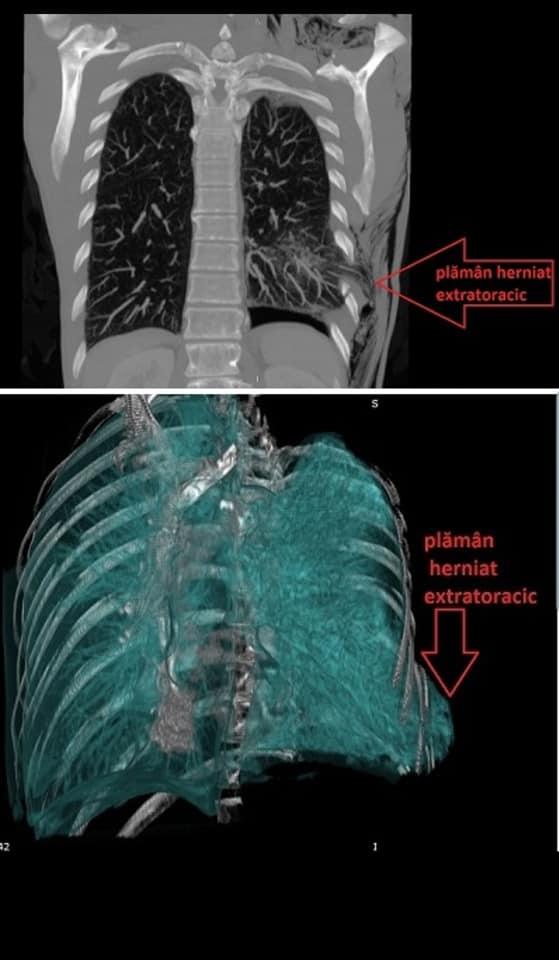

Medicii de la Spitalul Universitar din București au intrat în operație. Când au văzut cine era pe masă, au rămas surprinși. "Practic îi ieșise plâmânul afară!"

foto: Spitalul Universitar București